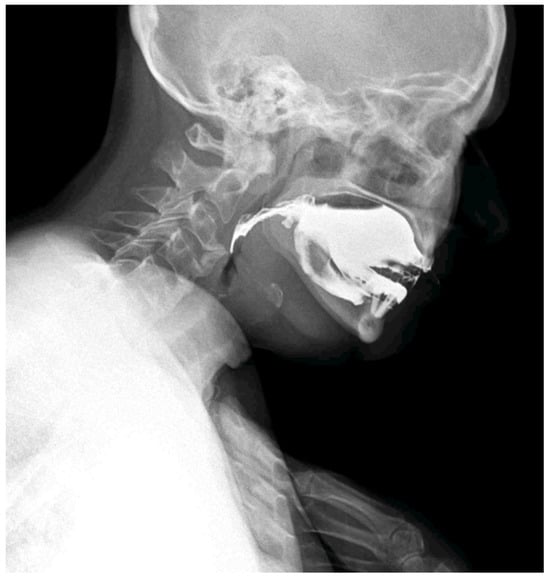

Figure 3. The patient adopted a compensatory swallowing position with neck and chest flexion forward to reduce pharyngeal narrowing and facilitate bolus passage. The pharyngeal lumen is narrowed by the anterior cervical osteophytes. Compared with traditional videofluoroscopic examinations, DDR offers a wider field of view, quantitative motion analysis, and significantly reduced radiation exposure [,,]. In the context of swallowing disorders, DDR allows simultaneous evaluation of bolus transit and the impact of mechanical obstructions, while also detecting compensatory strategies adopted by the patient. Moreover, DDR technology is available on portable equipment; this allows the clinicians to conduct a swallowing study directly at the patients’ bed, which is particularly important when dealing with frail patients affected by dysphagia and silent aspiration. The whole dynamic acquisition captured at 15 frames/s is presented in Supplementary Material S1.

Figure 4. The compensatory position with the anterior flexion of the neck and chest is effective in slightly reducing the compressive effect of the osteophyte and ligament calcification to enable the contrast bolus passage (white arrow).

Figure 5. The compensatory position with anterior neck flexion (B), allows the patient to increase the pharyngeal diameter at the level of the narrowing related to the C2 osteophytes, compared to the neutral neck position (A).